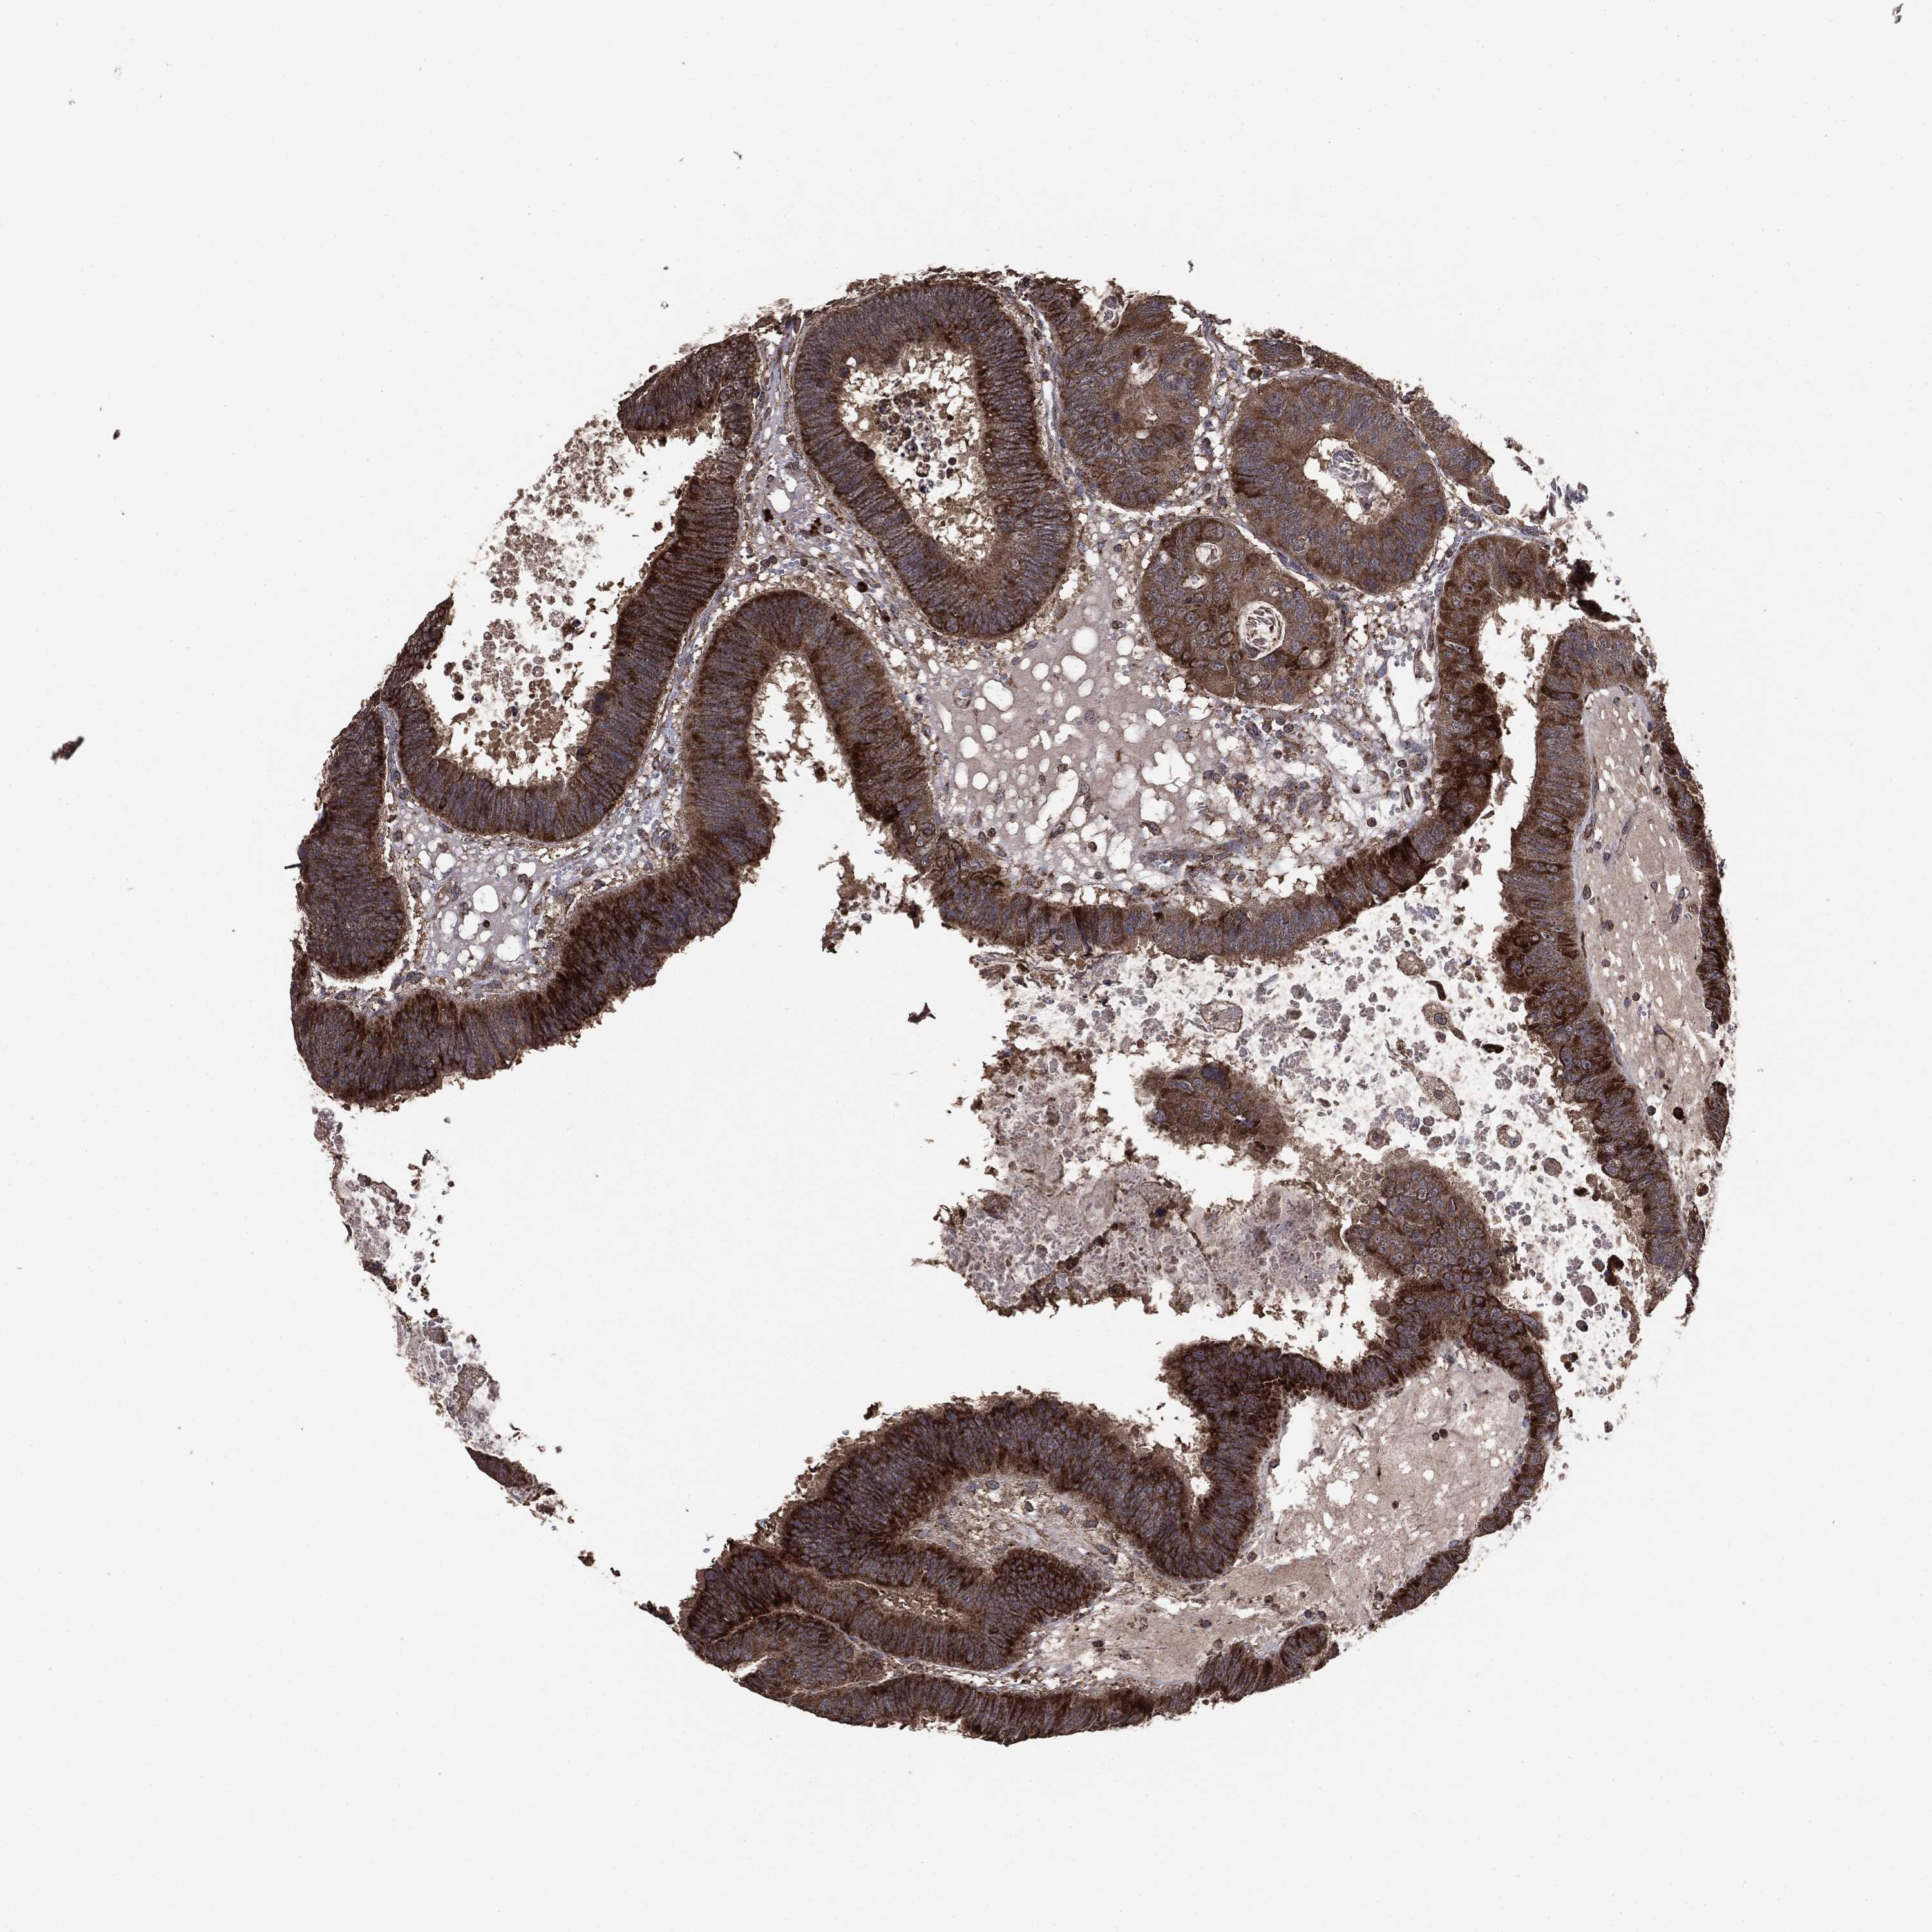

CANCER COLORECTAL CANCER Show tissue menu

ANTIBODIES

AND

VALIDATION